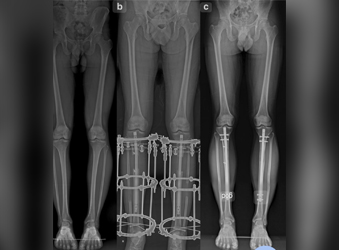

Deformity correction using the Ilizarov method is a surgical procedure that involves the use of an external fixator to realign bones and joints in the body.

Dr. Suhas Shah has been practicing as an orthopedic surgeon with super specialization in Ilizarov surgery since last 16 years. He is visiting as an Ilizarov specialist all over Maharashtra and has done more than 1400 surgeries in this specialty till now. I have been a faculty member during various Ilizarov courses & workshops held all over India.We now have a center for total Orthopedic care under one roof.

Dr. Suhas Shah is a renowned orthopedic surgeon from India who has extensive experience in using the Ilizarov technique to treat various congenital deformities in children.

At Dr. Suhas Shah Orthopedic Center, we provide comprehensive orthopedic and trauma care under one roof, specializing in advanced techniques like Ilizarov surgery and limb lengthening & reconstruction. With over 16 years of experience, Dr. Suhas Shah has performed more than 1,400 Ilizarov surgeries and serves as a visiting Ilizarov specialist across Maharashtra.